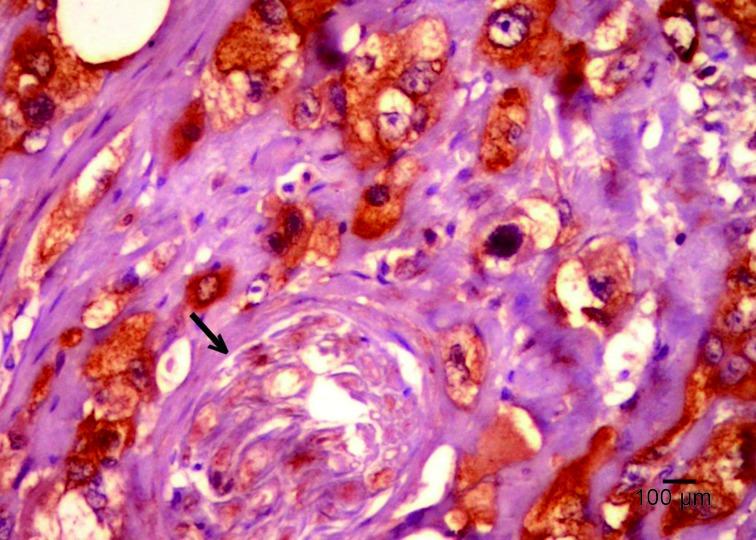

Mucoepidermoid carcinoma (MEC) is the most common primary malignancy of the salivary glands. Insulin-like growth factor-II mRNA-binding protein-3 (IMP3) is an important prognostic factor in some cancers and a tool that differentiates between benign and malignant pancreatic lesions. This study aimed to identify a relationship between the expression of IMP3 and the outcome of salivary gland MEC, as well as to differentiate MEC from pleomorphic adenoma (PA).

METHODS

Tissue specimens from 70 cases of salivary gland MEC, 40 cases of PA, and 10 cases with normal salivary gland were examined immunohistochemically for IMP3. The association among the expression of IMP3, clinicopathological characteristics and patient's survival was assessed.

RESULTS

IMP3 was present in 51.4% of MEC but absent in PA and normal salivary gland tissues. IMP3 expression was associated with age > 60 years, submandibular gland tumors, tumor size > 4 cm, high-grade tumors, lymph node metastasis, involvement of surgical margins, perineural invasion, distant metastasis, advanced TNM stage, tumor relapse, and death ( P<0.05). Increased expression of IMP3, tumors of the submandibular gland, and lymph node metastasis were independent prognostic factors of -free survival (DFS). In addition, IMP3 was a strong predictor of overall survival (OS) together with distant metastasis and intermediate and high-grade tumors.

CONCLUSIONS

IMP3 expression is highly important in evaluating the outcome of MEC. IMP3 can be used to differentiate MEC from PA of salivary glands.